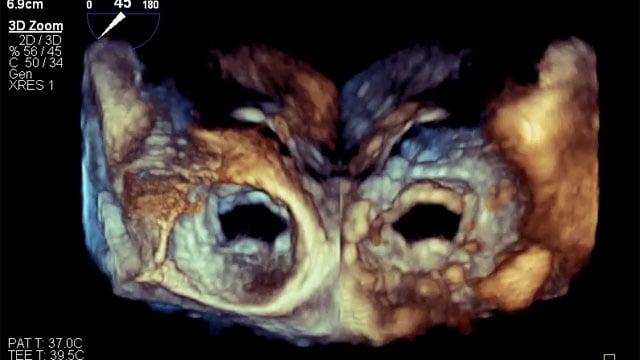

Severe MR in a high-risk patient with a suboptimal anatomy for M-TEER: what other options can we find?

Multimodality imaging reveals fibro-calcific leaflet disease, restricted motion, and a short posterior leaflet, making him a suboptimal candidate for M-TEER and prompting consideration of transcatheter mitral valve replacement. How would you treat?